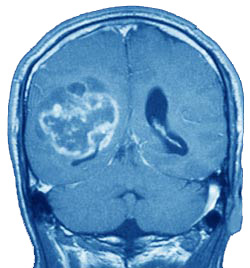

Una ricerca italiana dona nuove speranze ai malati di glioblastoma o GBM, una grave forma di tumore al cervello, tra le più comuni tra le neoplasie del sistema nervoso centrale, che nel nostro paese colpisce più di settemila persone, soprattutto tra gli over 50.

L’ultima scoperta nella lotta ai tumori, viene da un team di ricerca italiano, degli Istituti di chimica biomolecolare e cibernetica del Cnr, dove sarebbe stato definito un meccanismo capace di bloccare la crescita del glioblastoma. Il dottor Vincenzo Di Marzo dell’Icb-Cnr che ha coordinato la ricercaa, avrebbe spiegato come nei giovani le cellule staminali nervose siano capaci di portare alla morte le cellule tumorali, perché in grado di contrastare la loro crescita migrando verso le cellule tumorali di glioblastoma multiforme, producendo specifici mediatori lipidici, i cosiddetti endovanilloidi, in grado di indurre la morte attivando i recettori dei vanilloidi, chiamati TRPV1, presenti in enormi quantità sulla superficie delle cellule tumorali. La definizione di questo meccanismo naturale, spiegherebbe anche perché questa malattia non si manifesta nei soggetti giovani.